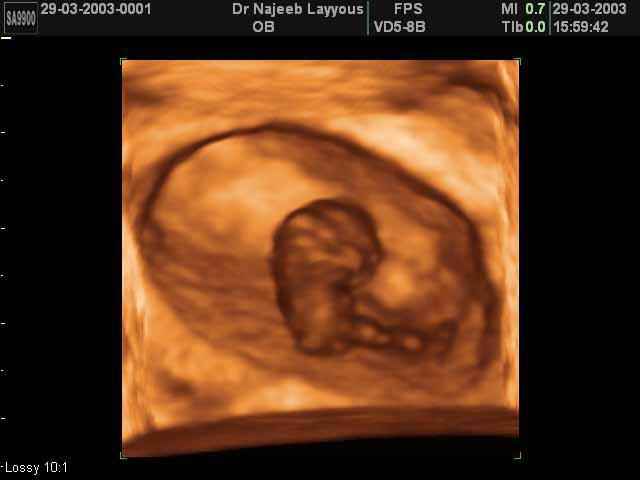

3D First Trimester Ultrasound Scan Photos